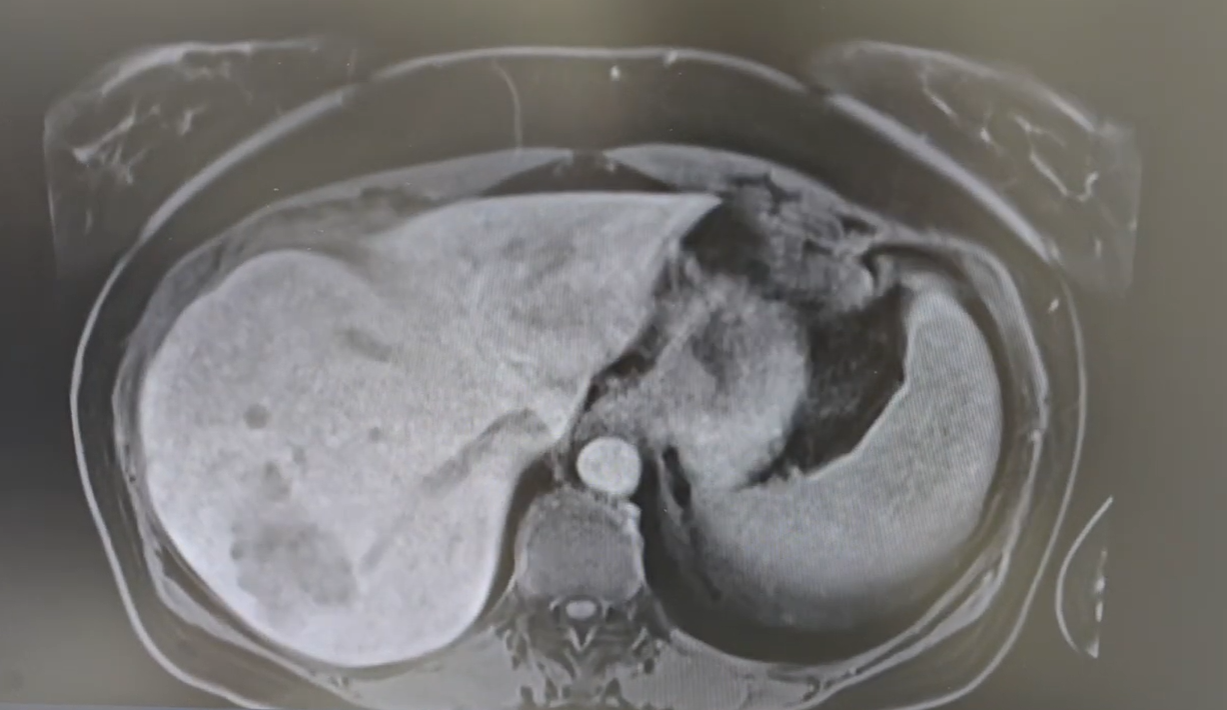

Navigating the Intricacies: How Anatomical Variations impact Major Hepatectomy

As experienced hepatopancreatobiliary (HPB) surgeons, we know that no two livers are exactly alike. While the general structure of the liver is consistent, the detailed vascular and biliary anatomy is subject to significant variations that impact the complexity and safety of a major hepatectomy. Planning for liver surgery is a highly personalized, critical step that […]